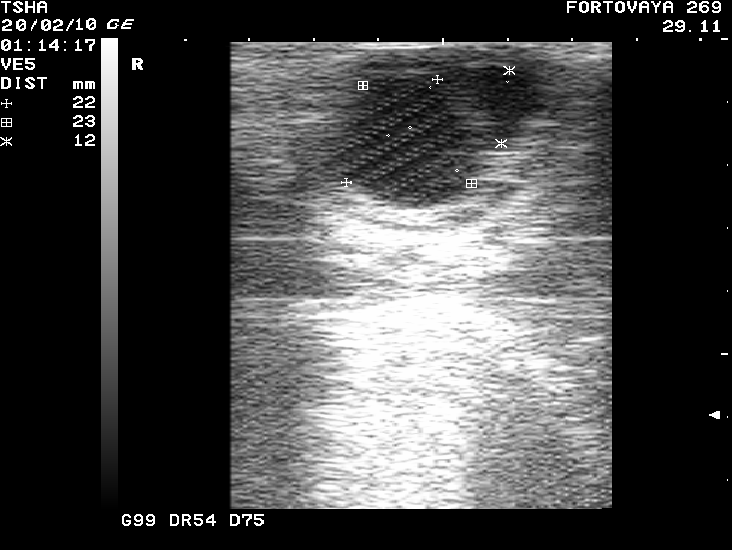

Рис. 6. Вариабельность параметров фолликуло - и кистогенеза у коровы Фартовая 269 с хронической формой кистозной болезни яичников. Сканирование яичников проводили через каждые 14 дней

При положительной реакции на лечение на 7-й день после введения овулина у 9-ти или 81,8% коров регистрировали формирование желтого тела солидного или кистозного типа в одном случае (9,1%) – образование двух желтых тел (рис.3), в другом – лютеинизацию стенки кисты с последующей ее регрессией и восстановлением овуляции.